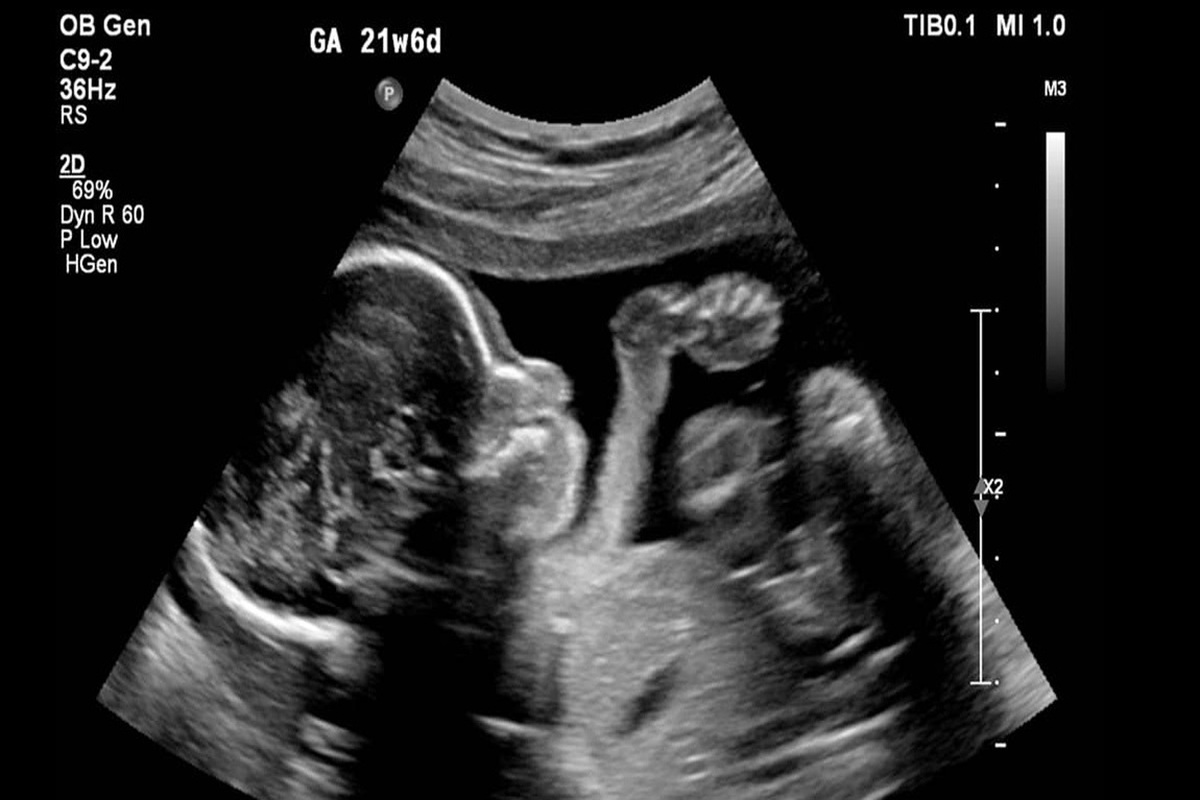

ارسال بیش از ۱۰۰ پرونده سقط‌ جنین غیرقانونی به مراجع قضایی

معاون درمان وزارت بهداشت با اشاره به راه‌اندازی و ابلاغ سامانه ملی باروری سالم، گفت: بیش از ۱۰۰ پرونده در زمینه سقط غیر قانونی، به مراجع قضایی ارسال شده و امیدواریم برخوردهای جدی و بازدارنده با این پرونده‌ها انجام شود.

وی درباره راه‌اندازی سامانه ملی باروری سالم، گفت: سامانه ملی باروری سالم ابلاغ شد. قرار است در قالب این سامانه از زمانی که تست حاملگی خانمی مثبت می‌شود و جنینی تشکیل می‌شود تا زمانیکه متولد می‌شود، در این سامانه ثبت می‌شود. به تدریج آزمایشگاه‌ها، پزشکان متخصصی و ... به این سامانه وصل می‌شوند و اگر احیانا نیاز به غربالگری باشد، در این سامانه ثبت می‌شود و اگر نیاز به سقط درمانی باشد، در این سامانه ثبت می‌شود تا بتوانیم یک جنینی را که تشکیل می‌شود تا زمان تولدش ردیابی کنیم تا این جنین‌ها از دست نروند و بتوانند به جمعیت سالم کشور اضافه شوند.